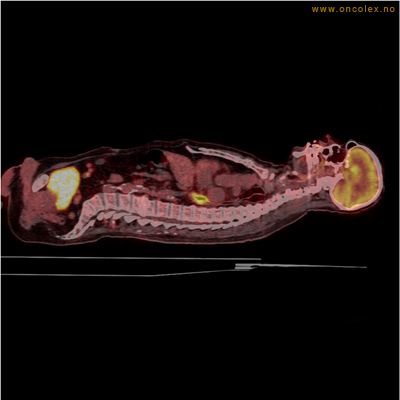

Eksempler på funn

Vev som tar opp mer radioaktivt stoff, synes som hvite områder som lyser opp mer i forhold til annet vev som tar opp mindre sukker.

Moderat opptak av FDG i bløtvevssarkom venstre halvdel av brystkassen. Områder med lavere opptak antas å skyldes dels betennelse som skyldes svulst, dels svulstnekrose.

Kraftig opptak i svulst i lunge.